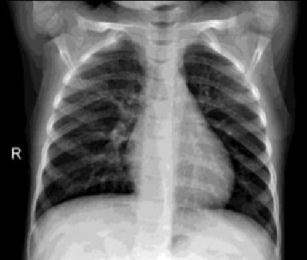

Fig.1:examplesoffrontviewchestX Rayimages.(a) NormalchestX rayimage,(b)Coronavirusinfectedchest image.

Fig.2:ViewofLungsCTScans

a)Normalx ray b)Covid19x ray